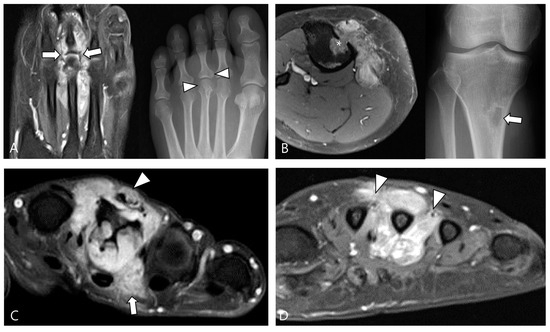

2.3. Morphological Findings for D-TSGCT

2.4. Relationship to Adjacent Structures of D-TSGCT

3.2. Differential Diagnoses of Extra-Articular D-TSGCT